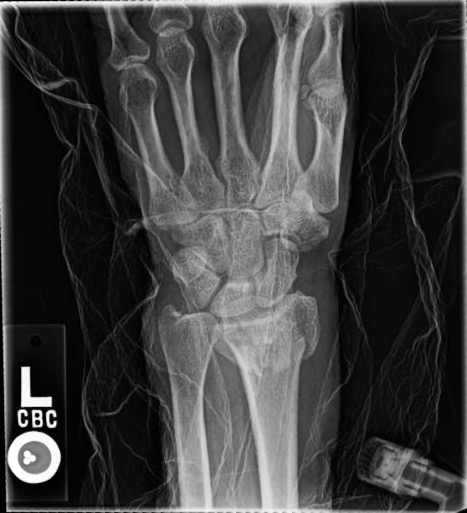

X-rays will be used to confirm the diagnosis. Fortunately, many of these fractures can be treated without surgery. Sometimes, the best thing is to push the fracture back into a better position and then hold it there with a cast. However, there are occasions where surgery is the best option. Surgery allows for the bones to be held in a better position more securely. With surgery, the bones can be held in place with pins, plates, and screws, and sometimes a combination of all of these. No matter the treatment, these fractures usually require at least 6 weeks to heal before it is ok to begin using the hand and wrist without restriction, but it often takes months before the pain and the stiffness fully resolve.

60-year-old female without other medical problems fell and landed primarily on her left hand and wrist. She had immediate pain and deformity at the wrist. She went to the emergency room where x-rays were performed showing her injury – a distal radius fracture. An attempt was made at improving the fracture position by the emergency room doctors and she was splinted. She was then referred to my clinic. She was seen soon afterwards. It was noted on new x-rays that the broken bone was in a less than ideal position. After a thorough discussion of the patient’s goals and concerns, surgery was felt to be the best option for her. Surgery was performed one week after her initial injury under general anesthesia. She was allowed to begin moving her wrist after her first post-operative visit 10 days after surgery and begin full weight bearing on the hand and wrist just under 6 weeks after surgery. She now has full function.